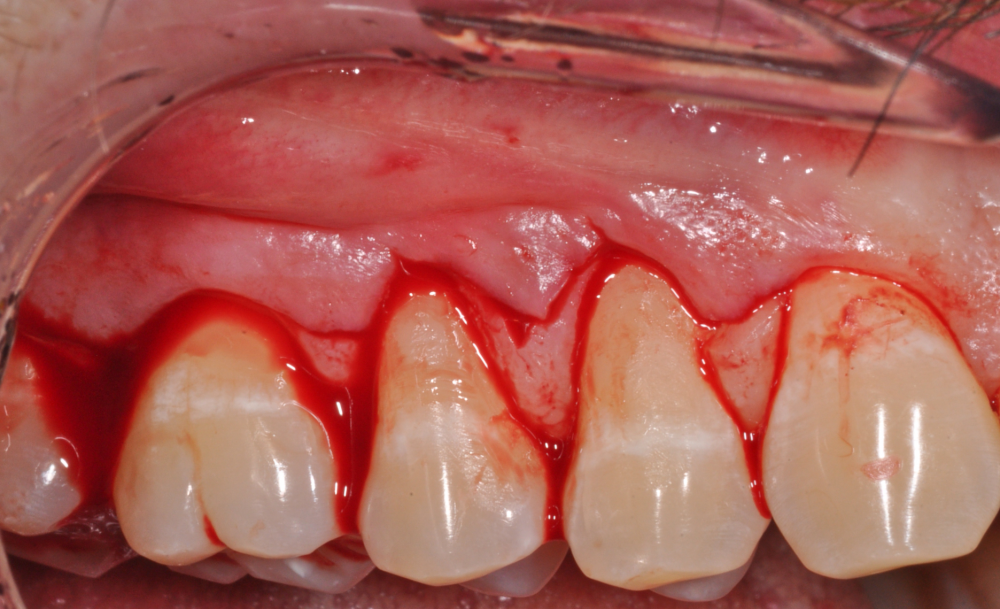

Treatment of periodontitis, periodontal regeneration, peri-implant regeneration,  mucogingival surgery around teeth and implants, resective surgery and multidisciplinary dental treatment are the main topics. The level of surgical skills is elevated up to the application of minimally invasive surgery with the adoption of surgical microscope.

This Advanced Training Workshop is a four-day immersion on the use of Operative Microscopes in Periodontal Regenerative Surgery to improve surgical outcomes and reduce patient morbidity. The use of this device contributes to the application of innovative clinical concepts and surgical tips. The paradigm shift to periodontal regeneration, higher esthetic standard, increased indications in mucogingival surgery propels the adoption of this advanced technology. It is primary responsibility and mission of the Cortellini Perio Academy to conduct high-quality research and high quality education to understand therapeutic benefits of the use of the operative microscope, disseminate micro-surgical knowledge through our educational structure involving masterly classes and hands-on training, and collaborate with the industry to develop user-friendly and efficient devices and instruments.

This Advanced Training Workshop will face the most challenging clinical problem in dentistry: the treatment of molars with furcation involvement. The “furcation dilemma” is still an open question with some clear answers and many dark sides. The aim of this 4-day full immersion workshop is to discuss the non-surgical and surgical approaches to give clinicians predictable solutions for the treatment of teeth with furcation involvement. The course will be empowered with ample discussion on the anatomic and diagnostic parameters to set a treatment plan. The “core” of the workshop will focus on detailed description of surgical concepts, surgical techniques, clinical tips, complications and failures. Lectures, 2D and 3D video demonstrations, hands-on training, practical exercises on simulators, and case discussion, will allow clinicians to upgrade their skills in the treatment of teeth with furcation involvement.

This Advanced Training Workshop will include many innovative clinical concepts and very many detailed clinical tips. The course is a 4 days immersion in the revisited and updated world of Biologically Driven Resective Surgery & Crown Lengthening. Preparation of the patient, design of the surgical approach, flap management, bone surgery, supracrestal tissue preservation and suturing techniques will be discussed in details. The novelties in the concept of “Biologic Width” will be shared, along with the relationship between the periodontal tissues and the cervical margin of restoration. The course will be empowered with detailed description of novel concepts, detailed clinical tips and analysis of pitfalls, complications and failures. The problems will be analyzed and the most advanced solutions will be discussed and shown on Dr Cortellini cases. Lectures, 2D and 3D video demonstrations, hands-on training, practical exercises on simulators, and case discussion, will allow clinicians to upgrade their skills in the application of resective surgery.